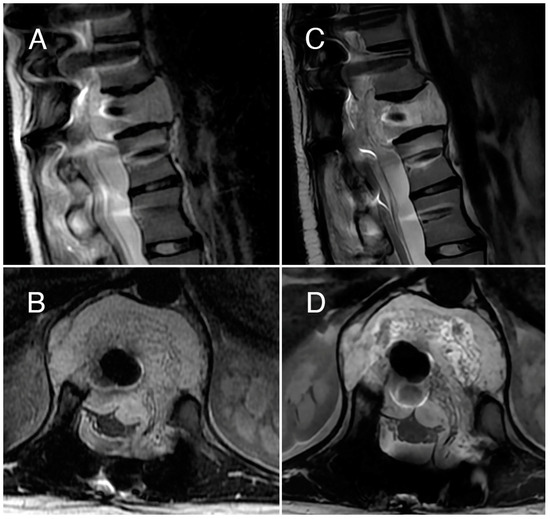

3.1. Case 1

3.2. Case 2